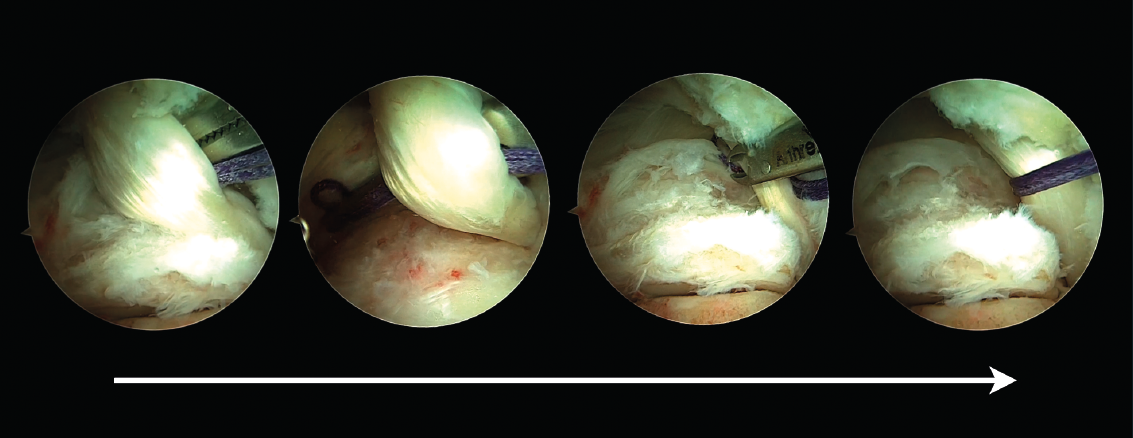

La sección del tendón FHL debe ser cuidadosa, con el objetivo de no poner en riesgo el paquete neurovascular tibial. La longitud mínima ideal del tendón FHL para su transposición al hueso calcáneo es de 15 mm. Antes de realizarse la sección del tendón, debe pasarse una sutura a su alrededor que permita con su tracción obtener la mayor longitud posible de tendón (Figura 2). Si al mismo tiempo de la tracción de la sutura se realiza una flexión plantar del tobillo y del hallux, aún se alcanzará mayor exposición del tendón, lo que permitirá conseguir mayor longitud del tendón.

Figura 2. Una sutura es pasada alrededor del tendón del flexor hallucis longus (FHL) para traccionarlo.

De acuerdo con las zonas descritas del tendón FHL(11), el tendón puede seccionarse en la zona 1 o 2. En la zona 1, el tendón se secciona justo antes de su entrada en la vaina fibro-ósea y con la ayuda de un bisturí o tijeras artroscópicas introducidas a través del portal endoscópico posterolateral. Alternativamente, el FHL puede seccionarse en su zona 2 a su paso bajo el sustentaculum tali. En este último caso, el artroscopio debe introducirse en la vaina fibro-ósea del tendón de FHL y, bajo visión artroscópica directa, el tendón se secciona con la ayuda de un bisturí de cirugía percutánea (bisturí de percutánea número 64) (Figura 3).

Figura 3. Sección del tendón flexor hallucis longus (FHL) en la zona 2. El artroscopio es introducido en la vaina fibro-ósea del tendón de FHL, el punto de sección es identificado con una aguja (visión superior), después es seccionado con un bisturí de cirugía percutánea (visión inferior).